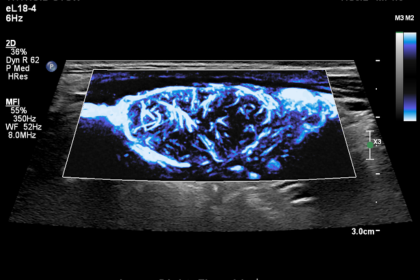

“One of the most exciting things about my work is that we are applying novel and emerging US-based techniques in a clinical setting, on clinical patients, in a variety of organs and using a variety of techniques,” Fetzer says. “From elastography, characterization of tissue attenuation and backscatter, or contrast-enhanced ultrasound qualitative and quantitative assessment, there are a wide range of US-based tools available now, with new techniques and novel applications emerging every year.”

As ultrasound systems have transitioned from analogue to digital processing, the field has moved toward truly quantitative assessment. “Whether it is measuring attenuation, characterizing backscatter, or estimating speed-of-sound in tissues, these measures give us additional added information of tissues and pathologies in vivo, dramatically increasing the amount of information we can extract beyond the simple greyscale images.” In contrast-enhanced ultrasound, time-intensity-curve analysis allows clinicians to assess tissue perfusion and monitor response to therapy.